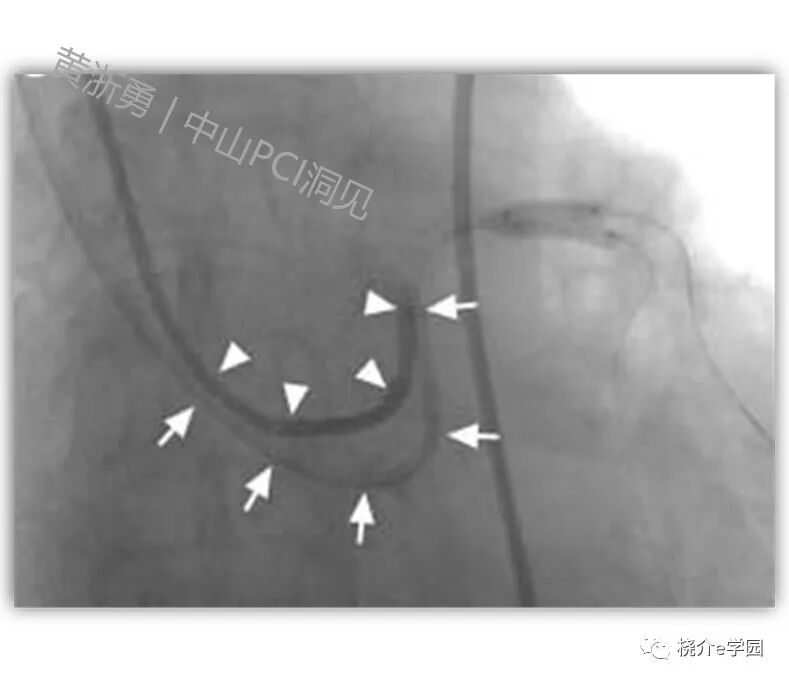

如下图示,左主干病变,两个球囊要对吻的时候,单根指引导管下不了两个大球囊,这时从另外一侧径路里面,再送一根指引导管过去。通过双指引导管技术,每一根指引导管里面下一个球囊,就能够轻松的完成手术。

双指引导管技术

应用双指引导管时,一个核心技术就是“乒乓到位”。如何理解呢?两根指引导管只能一根到位,另外一根要脱离冠脉口,两根同时到位的话,有可能损伤冠脉口,导致夹层。